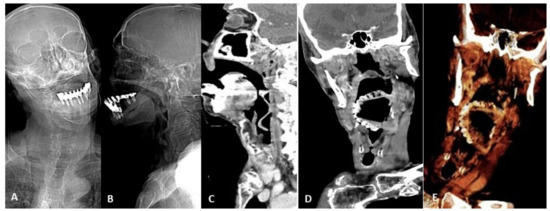

2. Device Identification and Recognition

3. Device Integrity and Migration